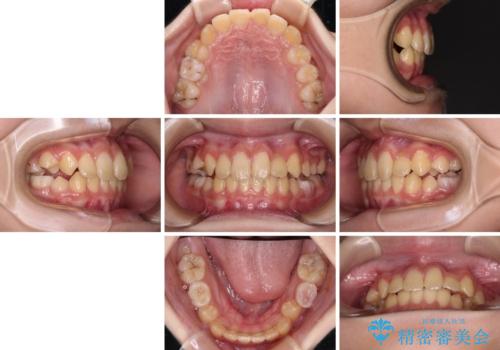

過剰歯を抜歯して前歯を排列 インビザライン・ファーストによる小学生のⅠ期治療

- 前歯の叢生を気にして来院された、小学校3年生女児の患者様です。

身長がやや低く、乳歯から永久歯への交換が少し遅い印象があったので、ワイヤー装置による1期矯正治療ではなく、乳歯も積極的に動かすことのできるインビザライン・ファーストにて治療を行うこととしました。

上顎前歯に過剰歯があったため、まずはその歯を抜歯し、傷が治癒したタイミングでインビザラインを発注することとしました。